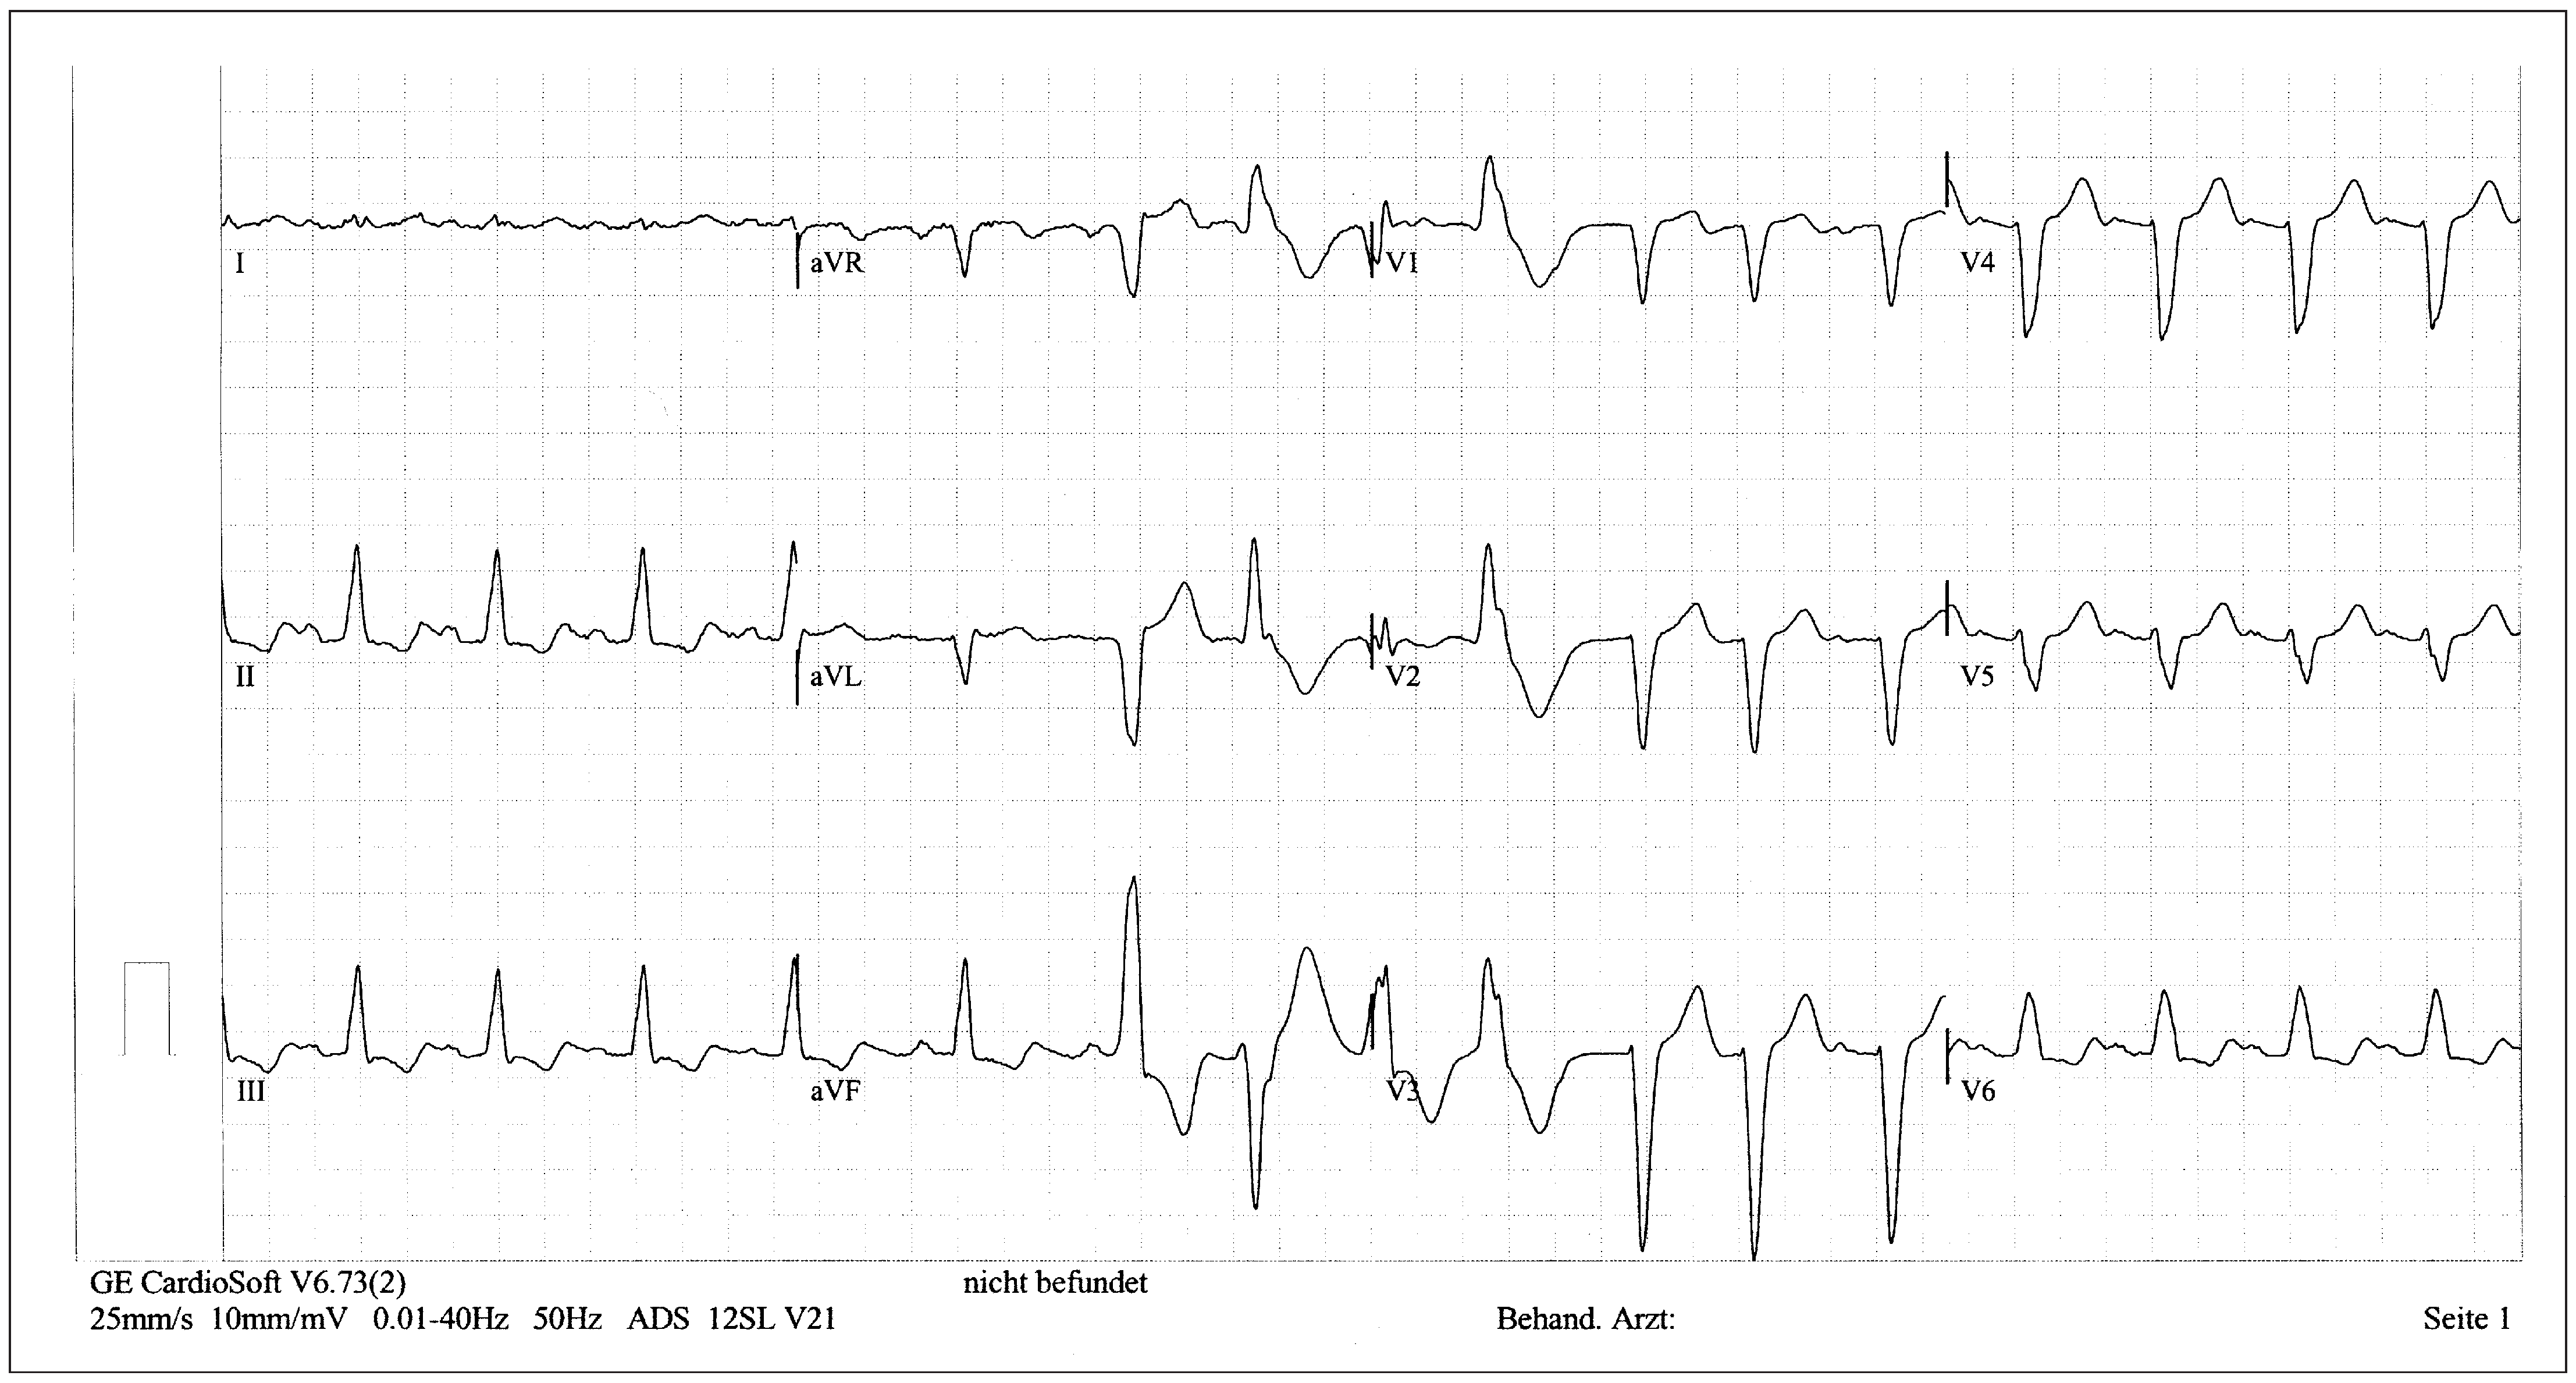

Patient